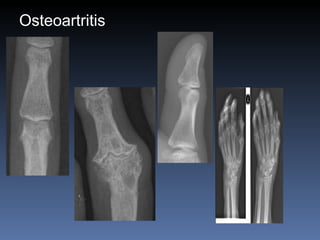

Osteoartritis IFDs, IFPs, 1 st  CMC Osteofitos Estrechez asimetrica del espacio articular  Esclerosis subcondral Quistes subcondrales No erosiones marginales Densidad osea preservada

Osteoartritis